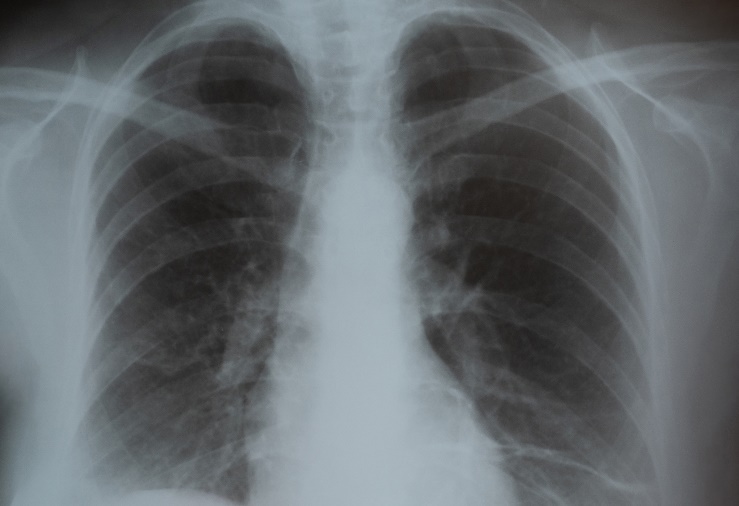

Lung Cancer Screening Action Team Presents: The Consortium in Action

The New York State Consortium’s Lung Cancer Screening Action Team (LCSAT) is made up of clinicians, researchers, educators, advocates, and organizations across the state who share the mission of decreasing the burden of lung cancer in New York State. The Action Team works to mobilize multi-level resources to increase lung cancer screening using guideline-driven, evidence-based strategies in an effort to save lives through early detection.